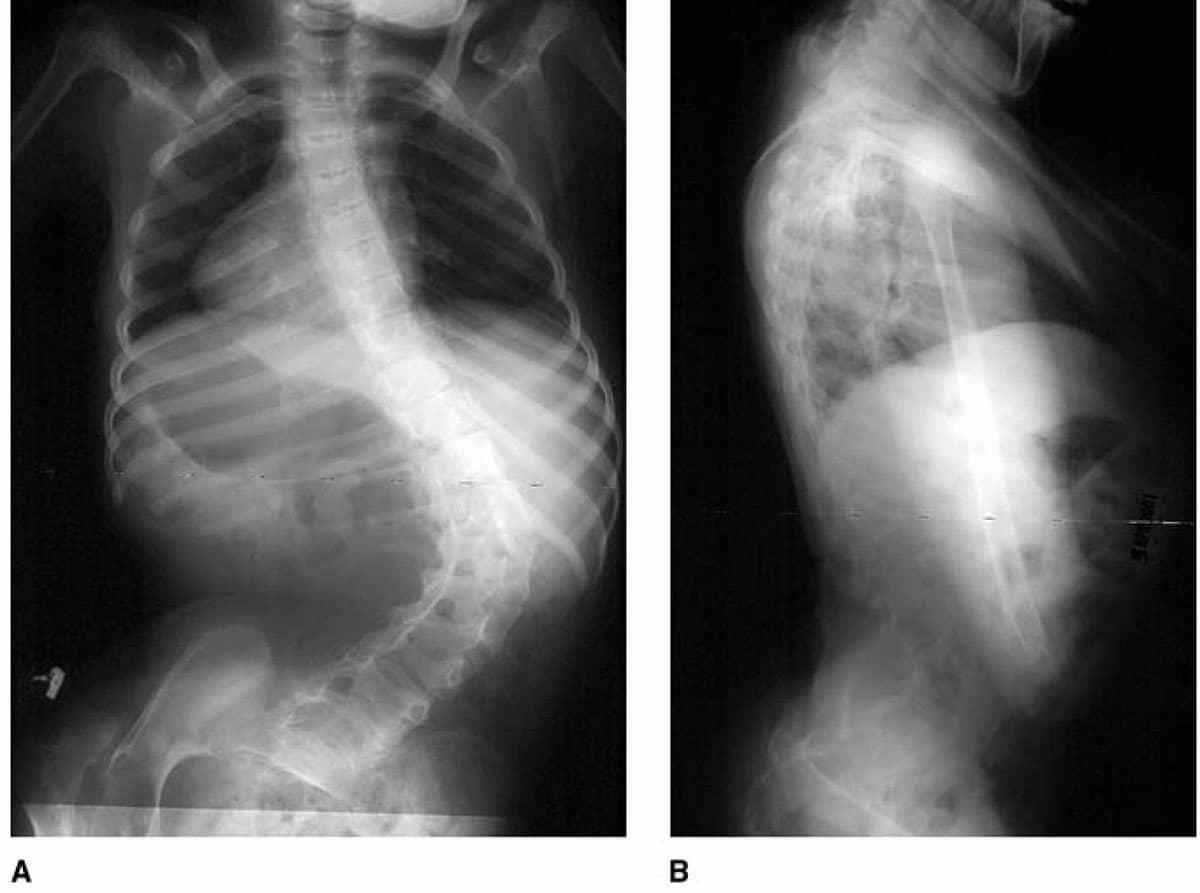

X-rays of a patient with cerebral palsy and scoliosis

(Left) X-ray showing the spine of a patient with cerebral palsy who has a sweeping 73-degree curve. (Right) A side view of the spine showing worsening lumbar lordosis (swayback), which may cause sitting imbalance and lead to pressure sores.

Reproduced from McCarthy J, D'Andrea L, Betz R, Clements D. Scoliosis in the Child With Cerebral Palsy. J Am Acad Orthop Surg. 2006; 14(6):367-375